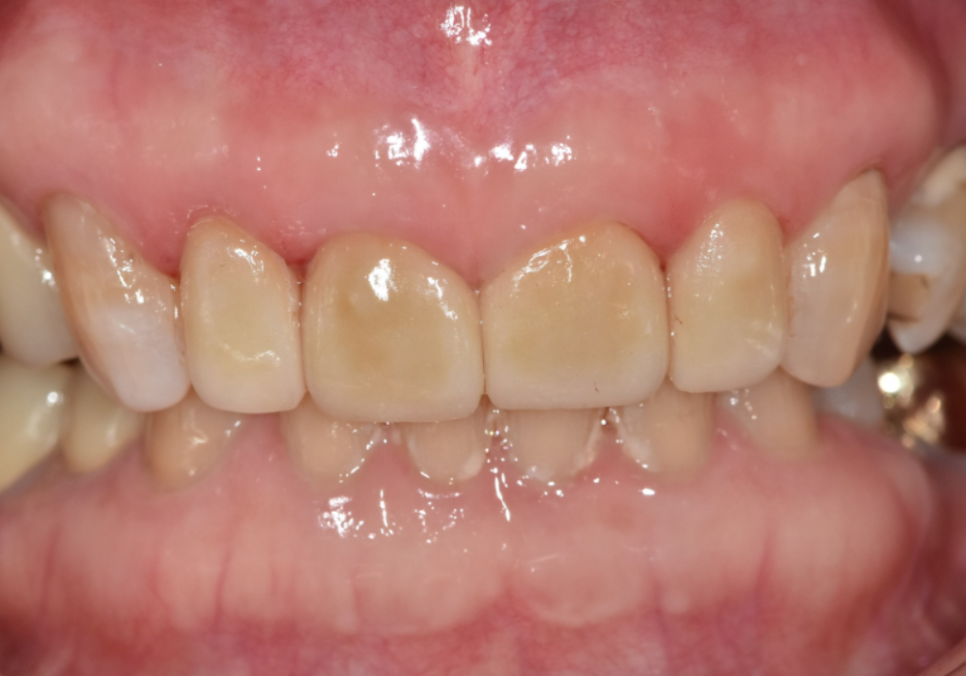

이 환자분은 70대 여성입니다.

젊을 때부터 앞니 사이가 벌어져 있었고

그 틈을 레진으로 메워 사용해 오셨다고 해요.

처음에는 괜찮았지만 나이가 들며

레진이 깨지고 떨어지는 일이 반복되자

“이번에는 제대로 고쳐보고 싶다”며 내원하셨습니다.

입안을 자세히 보니

앞니 사이를 메운 레진이 깨져 있었고,

그 양옆 작은 앞니가

다른 치아보다 눈에 띄게 작았습니다.

250304

이렇게 주변 치아보다 유난히 작은 치아를

‘왜소치’라고 부릅니다.

왜소치는 크기가 작다 보니

그 주변으로 공간이 남기 쉽고,

결국 앞니 사이가 더 벌어져 보이는 원인이 됩니다.